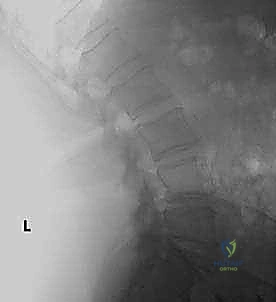

* الأشعة السينية (X-rays): خاصة الصور الديناميكية (أثناء الانحناء للأمام والخلف) لتقييم درجة عدم الاستقرار الميكانيكي والانزلاق.

* التصوير بالرنين المغناطيسي (MRI): المعيار الذهبي لتقييم الأنسجة الرخوة، ورؤية الأقراص الغضروفية، والأعصاب، والحبل الشوكي، وتحديد مكان الانضغاط بدقة متناهية.

* التصوير المقطعي المحوسب (CT Scan): يوفر صوراً ثلاثية الأبعاد للعظام، وهو ضروري جداً للتخطيط الجراحي الدقيق وتحديد أحجام المسامير المناسبة لكل سويقة فقارية.